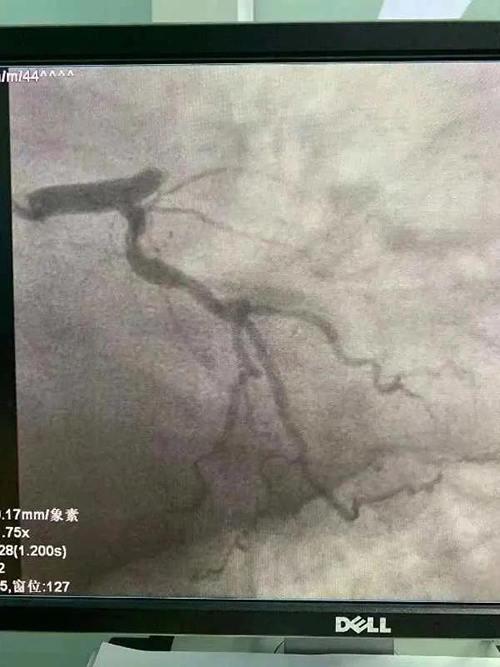

这边,救护车飞速行进;那边,急诊科、CCU病房与救护车时时视频联网,观察、指导;同步,CCU医生兵分两路,一路火速赶往急诊科会同急诊医生做好接诊准备,一路赶赴导管室做术前准备。18:00,救护车到达胸痛中心门前,绿色通道开通,救护队员、急诊科医生、CCU医生推着患者一路小跑奔向电梯,电梯立即接力到达导管室,进入导管室手术间,立即行造影检查,进一步确诊并确定病变部位,随后迅速为患者实施血栓抽吸术和冠脉介入手术。18:18分,血管开通!

从入院到血管开通(D-to-B)仅用时18分钟!

目前,辽阳市中心医院胸痛中心常规开展冠状动脉造影术、球囊扩张术,冠状动脉支架植入术、血栓抽吸术,冠脉内溶栓术,心脏起搏器植入术、主动脉球囊反搏术等心血管疾病介入诊疗技术及其他急危重症患者规范化治疗,年完成冠脉介入手术1200余例,起搏器手术50余例。